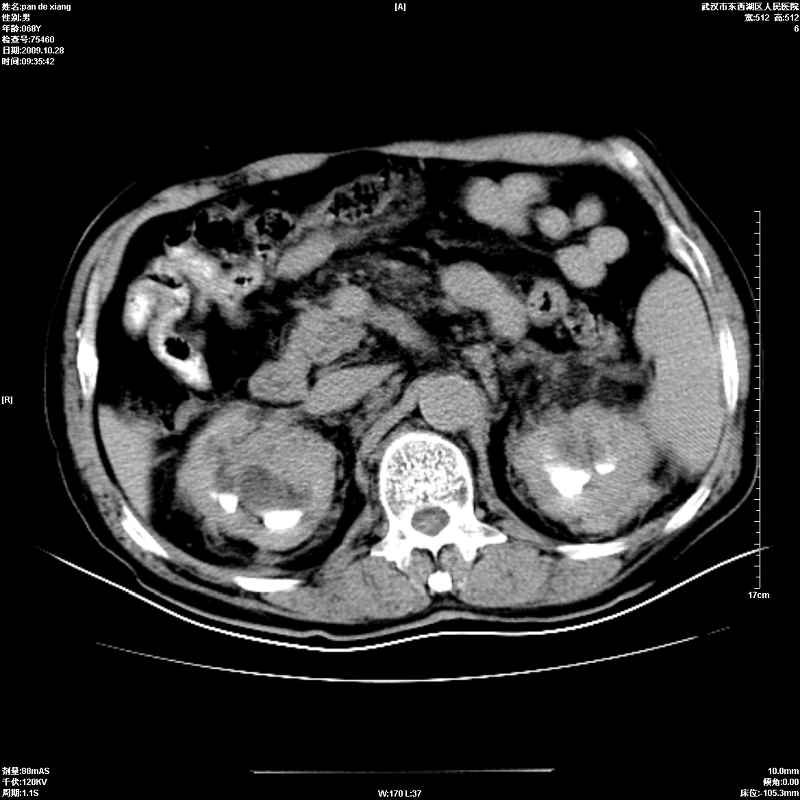

以下是引用杀毒软件在2009-10-28 20:41:00的发言:[br]结合临床考虑---白血病双肾改变或淋巴瘤。

以下是引用zxl51642在2009-10-29 9:59:00的发言:[br]结合临床“单克隆免疫球蛋白血症”,考虑双肾为继发损害并肾功能不全(尿中大量igg及少量iga、igm等大分子免疫球蛋白滤出所致继发损害),椎前软组织肿块为髓外造血。与浆细胞瘤有区别,平扫时有战友说的很清楚。